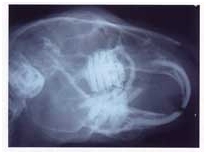

bien visible sur la radiographie de la figure 2

Figure

2 : Radiographie d'une tête de lapin

Toutes les dents des lapins sont à

croissance continue, aussi bien les incisives que les molaires et

prémolaires. Par exemple la croissance des incisives supérieure est de 2

mm par semaine et celle des incisives inférieures de 2,4

mm par semaine. Celle des dents jugales (prémolaires et molaires) est

nettement moins forte : environ 2

mm par mois. Pour permettre cette croissance continue, les dents ont une

"racine" creuse partant du bourgeon dentaire profond. La cavité

est occupée par la pulpe dentaire abondante qui va presque jusqu'à

l'extrémité externe de la dent. La longueur de la partie "buccale

" de chaque dent (visible dans la bouche) est beaucoup plus faible que

sa partie gingivale (incluse dans la gencive). Cette caractéristique est